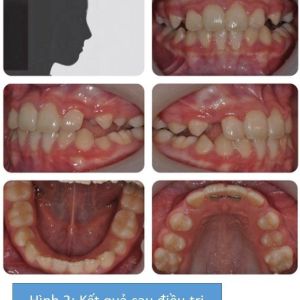

Việc điều trị nên hướng đến 2 vấn đề nổi bật nhất: độ cắn chìa âm và mất khoảng trống ở vùng răng hàm nhỏ thứ 2 hàm trên. Do đó, sử dụng khí cụ edgewise sẵn thông số phân đoạn ở hàm trên để phân bố lại khoảng ở cung răng trên, cho phép các răng hàm nhỏ thứ 2 hàm trên mọc lên và các răng cửa hàm trên thẳng hàng. Thêm vào đó, headgear kéo ra trước nên được sử dụng cùng với khí cụ chức năng để dễ dàng chỉnh sửa tương quan răng cửa. Headgear kéo trước cần được đeo ít nhất 14 tiếng mỗi ngày để tạo ra sự thay đổi đáng kể.

Kết quả được thể hiện ở hình 2.